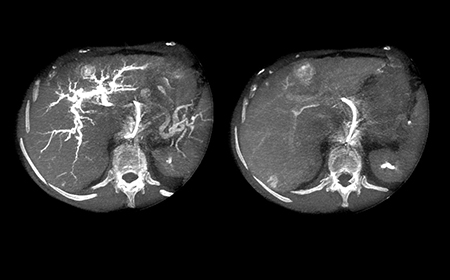

Решение DualPhase Imaging Решение для визуализации DualPhase Imaging обеспечивает визуализацию сосудистых структур, присутствующих в исследуемой области в артериальной фазе, и накопления контрастного вещества в отсроченной фазе.

С развитием двухфазной КТ-подобной визуализации действительно больше нет необходимости в комбинированном применении систем ангиографии и КТ либо ангиографии и МРТ.